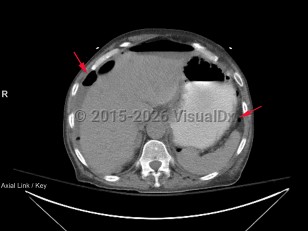

Bowel perforation

Causes of perforation include peptic ulcer disease (mostly duodenal), small and large bowel malignancies with tissue invasion, acute diverticulitis, acute appendicitis in the elderly population, inflammatory bowel disease (Crohn disease, ulcerative colitis), trauma, consequence of ischemic injury, and ingestion of foreign bodies (including fish or poultry bones), or it may occur as a complication of endoscopic procedures.

A patient will typically present with abdominal pain as well as signs of severe inflammatory response syndrome (SIRS criteria). The patient may have an acute abdominal examination with a rigid abdomen and minimal to no bowel sounds, although the examination can be misleading and may be unremarkable (particularly in immunocompromised patients or those on steroids).